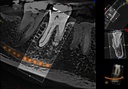

Introducing the CS 9300 Premium Panoramic, Cephalometric, and Cone Beam System from Carestream Dental – your ultimate solution for top-quality dental imaging. This state-of-the-art machine offers both 2D panoramic and cephalometric dental X-rays, as well as adjustable 3D cone beam images in up to seven different field of view sizes, extending up to 17x13.5 cm. This comprehensive range of imaging capabilities makes it a versatile tool, perfect for supporting a wide array of dental, surgical, or orthodontic examinations.

With the CS 9300 Premium, you can expect unparalleled image clarity and precision, allowing you to confidently diagnose and plan treatments with ease. Whether you're performing routine dental check-ups, complex surgical procedures, or orthodontic assessments, this system ensures outstanding results.

The CS 9300 is a multimodality imaging system that offers a wide range of 2D and 3D imaging options.

The CS 9300's 2D panoramic x-ray imaging capabilities are powered by variable focal trough technology, which provides optimal clarity for every image. The system's 3D imaging capabilities are based on cone beam technology, which delivers high-resolution images with a low radiation dose.

- Endodontics